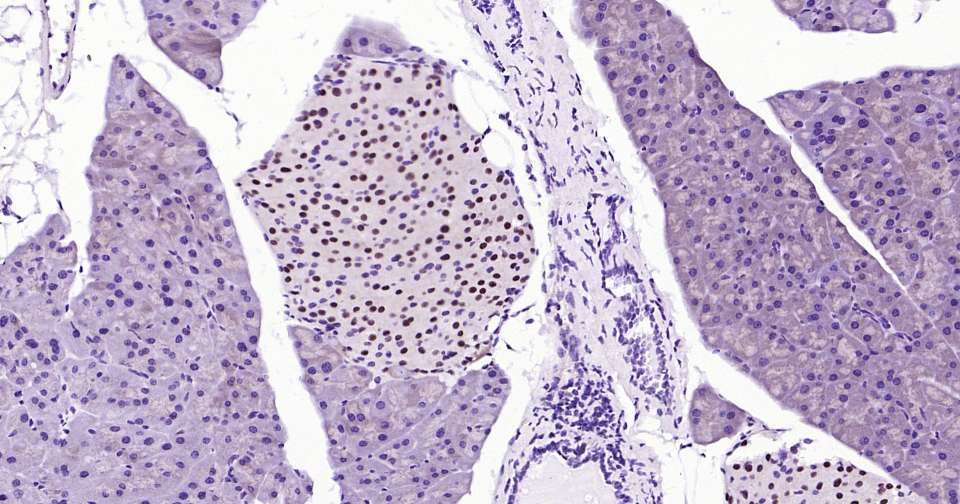

Immunohistochemical analysis of paraffin embedded mouse pancreas tissue slide using IHC0367 (PAX6 Kit).